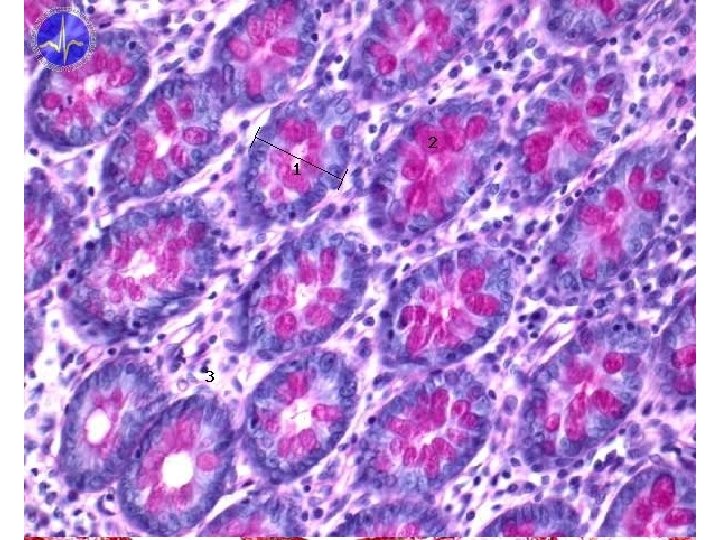

Tunica mucosa of small intestine • plicae circulares (Kerkringi) villi intestinales microvilli • glandulae intestinales = Lieberkühn´s crypts • simple columnar epithelium • lamina propria mucosae – vessels, smooth muscles, noduli lymphoidei

Cells of small intestine mucosa • enterocytes - resorption – microvilli, interdigitations, lipid droplets • goblet cells – mucus production • Paneth cells – lysozym production • endocrine cells (DNES) - 12 types – cholecystokinin, sekretin • M-cells - over noduli lymph. aggregati (Peyer‘s plates) • undiferentiated cells

Villi intestinales • • • digit- to leaf-formed elements about 10 times surface enlargement surface – enterocytes, goblet cells smooth muscle „skeleton“ capillary network lymphoid (=lacteal) inhte centre

Other layers of small intestine wall • tela submucosa – duodenum – glandulae duodenales Brunneri • tuboalveolar mucinous • alcalic secretion – ileum – noduli lymphoidei aggregati („agmina Peyeri“) = Peyer´s plates • accumulation of lymphoid tissue • other layers correnspond to the standard form of the tube